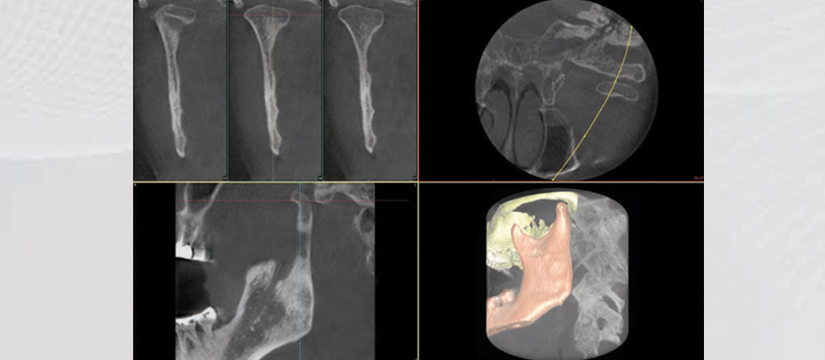

Klinika jonë premton se do t’ju ofrojë gjithnjë cilësinë më të lartë të shërbimit, me fjalën më të fundit të teknologjisë. Së fundmi ne jemi pajisur me pajisjen OWANDY IMAX TOUCH 3D. Kjo pajisje siguron me thjeshtësi dhe efikasitet imazhe high-definition për një diagnostikim të pagabueshëm. OWANDY është lideri i prodhimit të pajisjeve radiografike dentare në Francë, Amerikë, Gjermani e më gjerë. Produkti më i ri i OWANDY I-Max Touch 3D siguron të gjitha shërbimet radiografike në një aparaturë të vetme.

Aparatura posedon 17 programe të ndryshme ku mund të behën incizime si:

- TMJ Gojëmbyllur

- TMJ Gojëhapur

- 3D TMJ Pozicioni majtas

- 3D TMJ Pozicioni djathtas